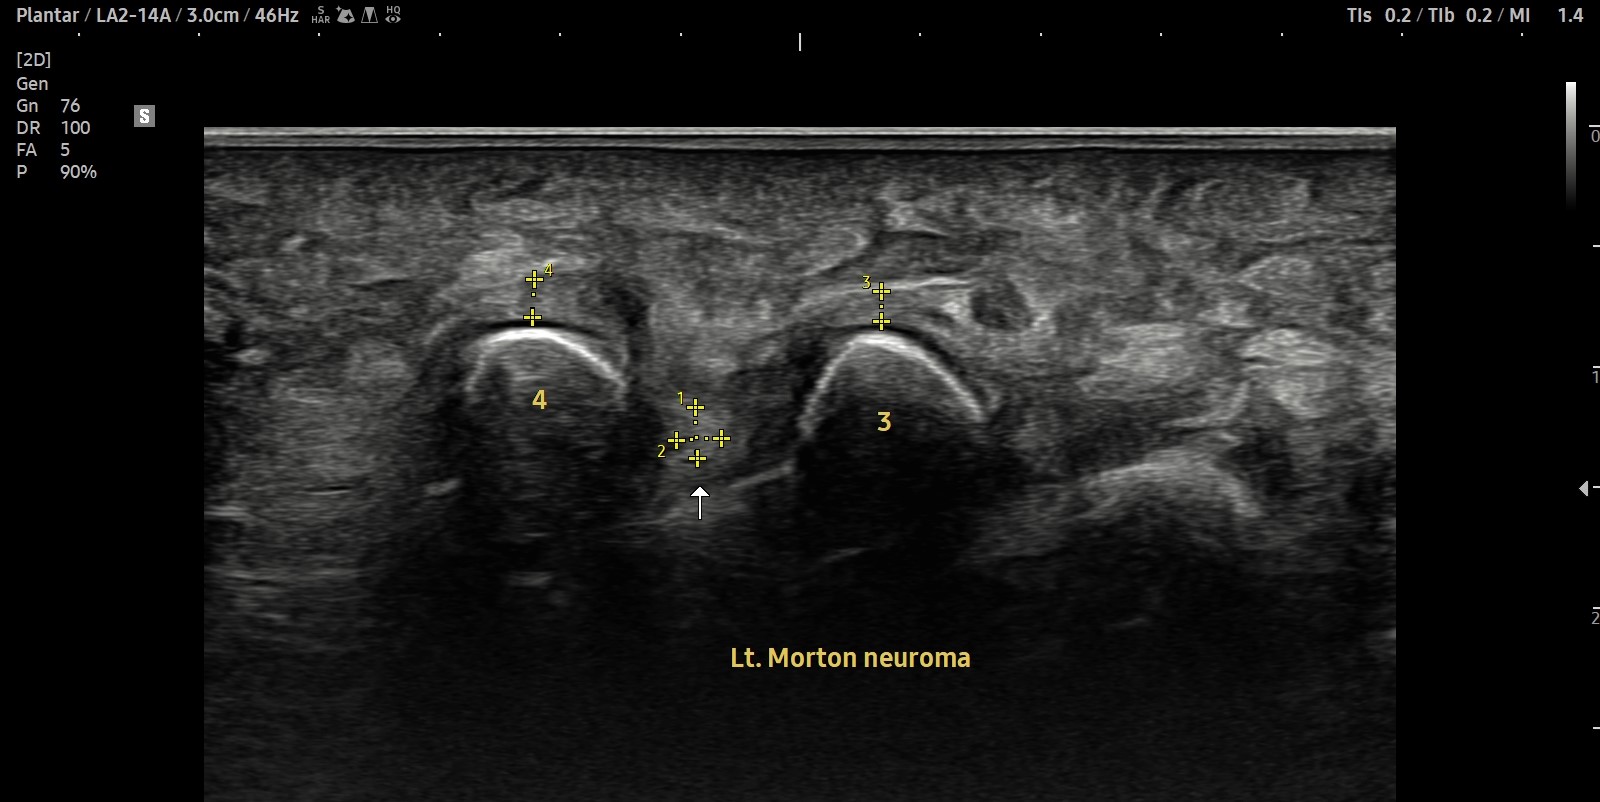

- 치료기간 : 2025. 7 . 4 ~ 2025 . 9 .1

- 치료횟수 : 10 회 (2cycle)

치료 전

치료 후